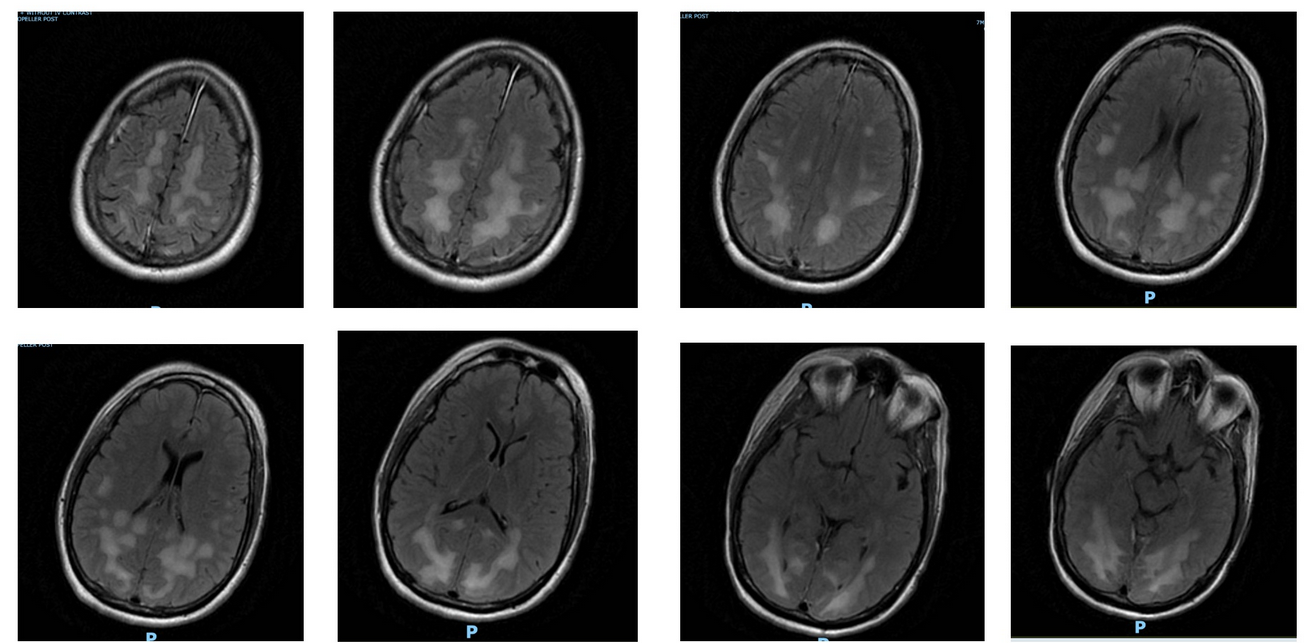

The toxic leukoencephalopathy from opioid fume inhalation is typically classified into three severity levels based on neurologic impairments: (1) mild: inattentiveness, confusion, ataxia, and psychomotor symptoms; (2) moderate: corticospinal or extrapyramidal involvement and impaired levels of alertness ranging from severe confusion to delirium; and (3) severe: generalized motor impairment, abulia without language disorders or apraxia, noticeable alertness deficits, and, in many patients, progression to death. There is no treatment-specific management for this toxic leukoencephalopathy. MRI findings of this toxic leukoencephalopathy include restricted diffusion in both globi pallidi and the cerebellum accompanied by symmetric hyperintensities on T2-weighted and fluid-attenuated inversion recovery images. The most common findings are bilateral, symmetric, periventricular white matter reduced diffusion, characteristically with symmetric involvement of white matter (the cerebellum and the posterior limb of the internal capsule). The injury is most severe in the cerebellum and cerebral hemispheres, superior cerebellar peduncle, tractus solitarius, and medial lemniscus.

T2-weighted fluid-attenuated inversion recovery images from MRI performed using a multisequence, multiplanar technique with and without IV contrast material.

His vital signs at presentation include a temperature of 37 °C, heart rate of 124/min, BP of 151/88 mm Hg, respiratory rate of 27/min, and SpO2 of 98% while breathing ambient air. On neurologic examination, he is alert and oriented to self, follows simple commands, but is inattentive. His voice is hypophonic, his speech is often incoherent, and he has evidence of occipital blindness on examination. He does not move his upper extremities, even to painful stimuli, and has limited movement in his lower extremities. Sensation to light touch and pain is intact. Emergency head CT scan reveals widespread cerebral and cerebellar white matter hypodensities and no intracranial hemorrhage. Lumbar puncture results demonstrate an RBC count of 2,000/µL (0.002 × 1012/L), WBC count of 11,000/µL (11 × 109/L), glucose level of 104 mg/dL (5.77 mmol/L) (serum, 129 mg/dL [7.16 mmol/L]), and protein level of 51 mg/dL; herpes simplex virus (HSV)-1 and HSV-2 polymerase chain reaction results are negative; Gram stain and culture results are negative; and Venereal Disease Research Laboratory (VDRL) screen results are nonreactive. Urine drug screening results are positive for opioids. Results from a comprehensive metabolic panel are all within normal limits. A 72-h continuous EEG does not show seizures. Results from MRI of the brain are shown in Figure 1.